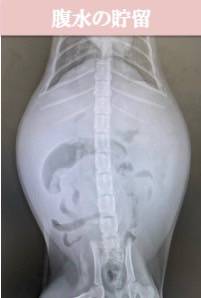

FIPは症状によってウエットタイプ、ドライタイプの2つの型に分けられます。

腹水や胸水が溜まってきます。腹水では腹囲膨満、胸水では呼吸困難が認められることが多いです。